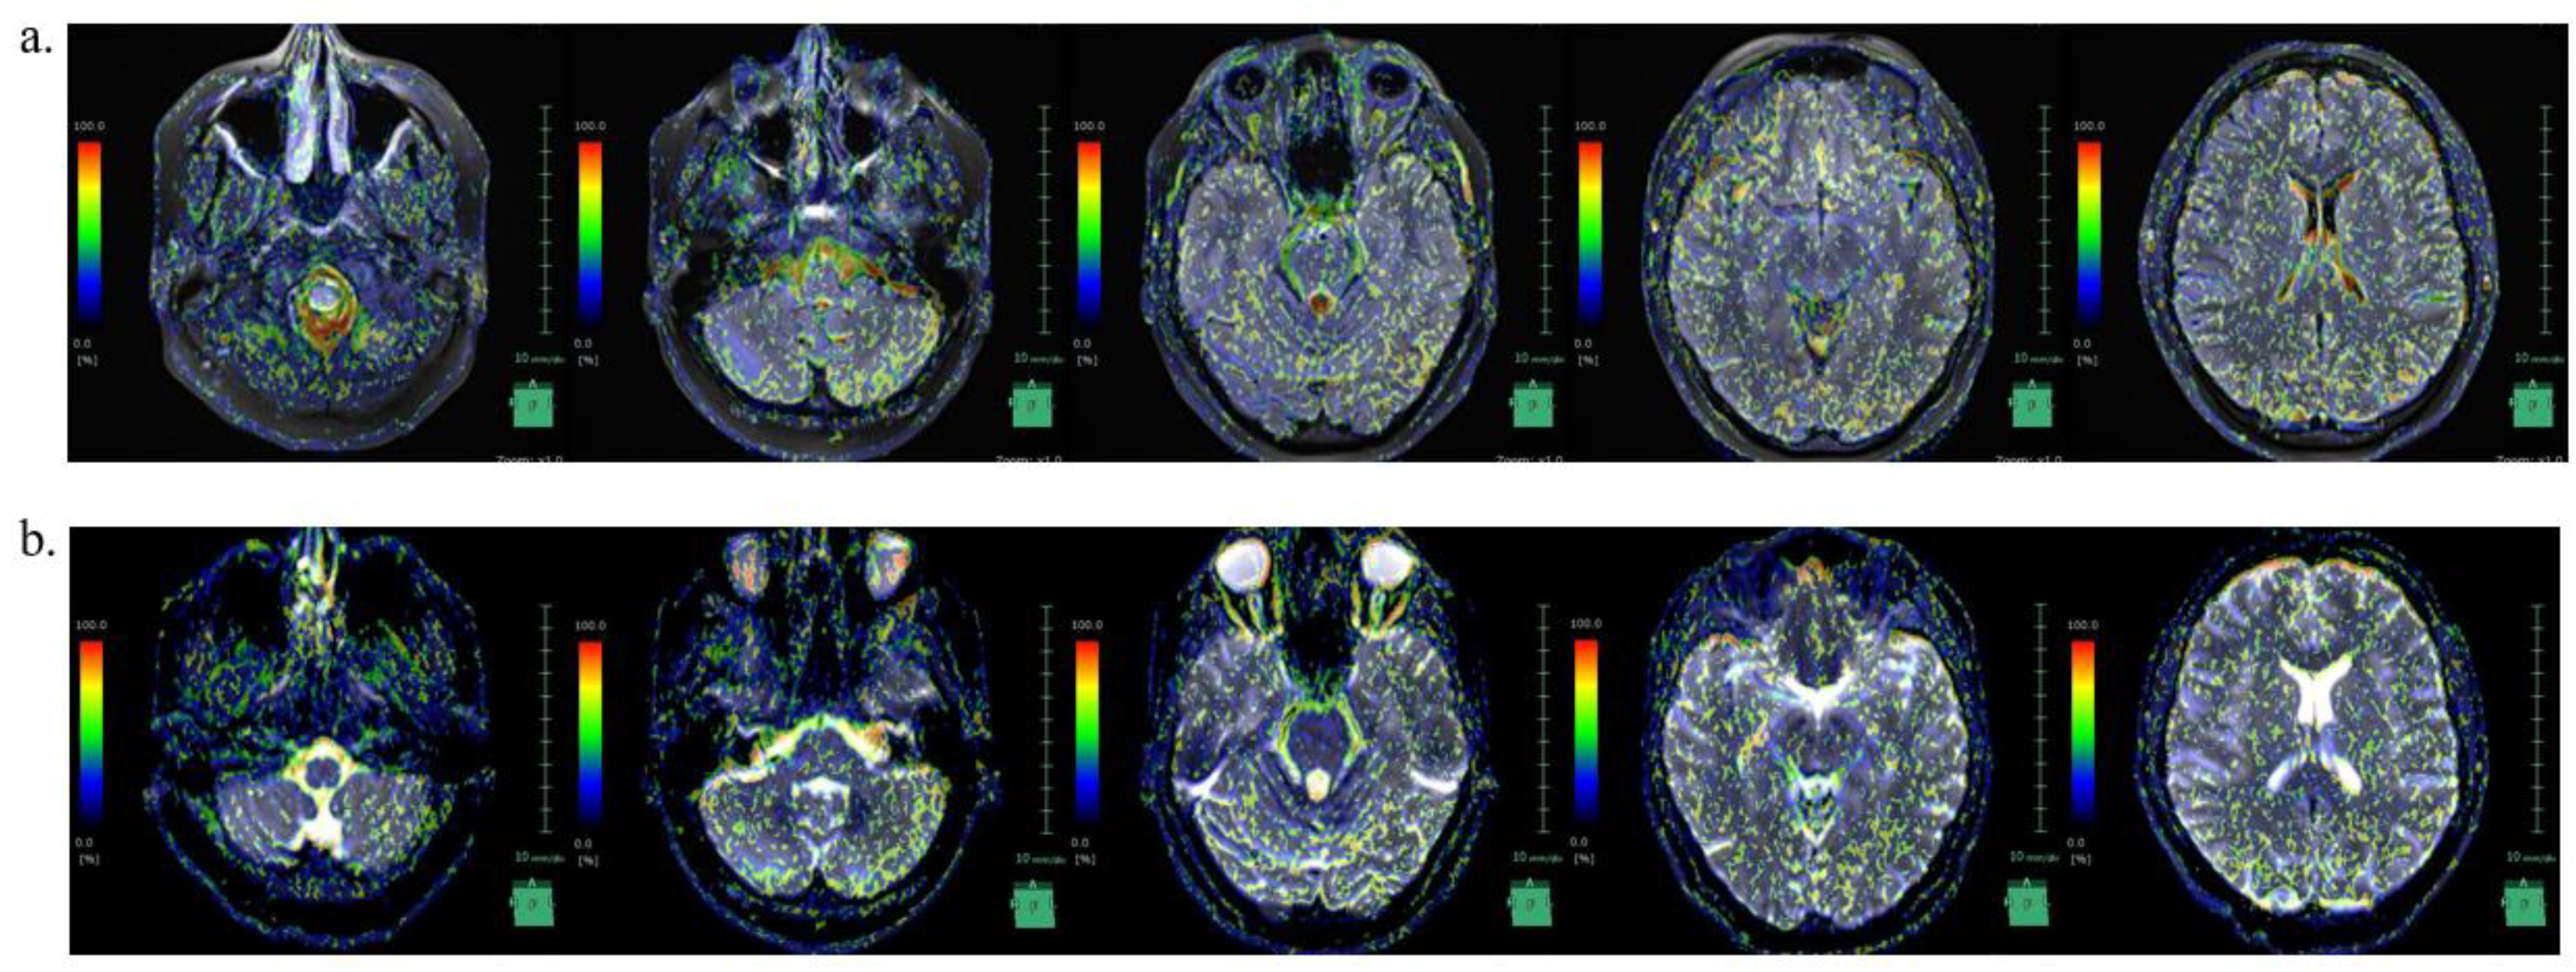

We were not able to find reports on CSF dynamics in IIH in the literature. Recently, IVIM MRI was used to visualize CSF movement [25]. CSF movement was visualized in our case as well (Fig 4). In this case, the SS site matched the area of strong incoherent CSF motion at the time of pre-treatment.

In the IICP condition, incoherent CSF movement was pronounced in the caudal portion of the medulla oblongata, fourth ventricle, lateral ventricles, and brain surface; however, in the decreased intracranial pressure condition following acetazolamide treatment, the incoherent movement in these regions decreased. In our case, the areas of SS coincided with areas of increased incoherent CSF motion before treatment, supporting the association between IIH and SS.

Figure 4. IVIM MRI findings showing intracranial hypertension state and intracranial pressure reduction with acetazolamide administration. a. IVIM MRI in intracranial hypertension state before oral acetazolamide, b. IVIM MRI showing decreased intracranial pressure after oral acetazolamide; IVIM MRI, intravoxel incoherent motion magnetic resonance